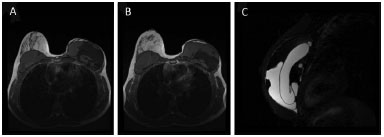

We found no studies in the literature on the main reason of the implant failure: rupture of the inner bag with mixture of the components (Figure 8). These cases were discovered by chance during the follow-up on patients with cancer. It is not related to any symptomatology, but causes a lot of psychological discomfort in patients after they acknowledge that they have a ruptured implant.

Figure 8. Component mixture of Becker expanders. MRI showing the component mixture with rupture of the internal capsule of the expander in the left breast, with mixture of the saline component with the silicone gel.